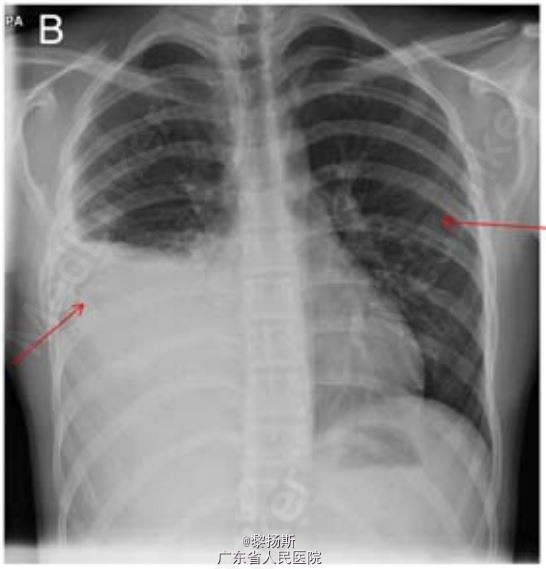

体查检查发现右侧胸部叩诊浊音,呼吸音减弱。复查胸片结果见图 1B。 首次就诊血液学检查白细胞计数正常,C 反应蛋白升高(303 mg/L)。患儿呼吸急促,需要吸氧 1-2L/min,同时对患者静脉用克拉维酸和克拉霉素。胸部超声证实存在大量胸腔积液,疑诊脓胸,遂转入我科进一步治疗。

诊断:骨性类外生骨疣相关性血胸;在超声介导下行右半胸腔穿刺引流,引流出 750 ml 深黑色的血性液体,而非脓液。除了收集右侧胸部的胸腔积液外,患者右侧第 4 肋前部末端可见一肋外生骨疣。同时第 5 肋连接处可见一结构畸形。另一个外生骨疣可见于左侧第 7 肋后部末端(图 2B)。患者曾多次手术切除位于膝部、肩部和前臂的良性骨性外生骨疣。右侧桡骨可触及一个质地不柔软的 3×2 cm 的骨性肿块。患者一直在整形外科随访,无骨痛或关节疼痛,本次发病前患儿无任何不适。无骨科疾病家族史。该患者接受抗生素治疗疗效较好,同时采用可视胸腔镜为患儿吸除血块和行胸腔冲洗。胸腔积液培养阴性。随后患者康复出院。

该病例旨在提醒医者们即使已经在胸片上发现明显的异常改变,仍应仔细查看胸片,在患儿初次就诊时就医者就忽略了外生骨疣这一改变。先天性多发性外生骨疣(HME)以及实性肋外生骨疣为肋外生骨疣的两种不同类型。HME 为常染色体显性遗传病,外生骨疣常见于四肢的长骨(图 3)。HME 患者的生长可能会受到限制,使得四肢长度不成比例,身材矮小。实性类外生骨疣患者则表现相反,外生骨疣常不对称性生长,无家族史。引自Thorax doi:10.1136/thoraxjnl-2015-207061